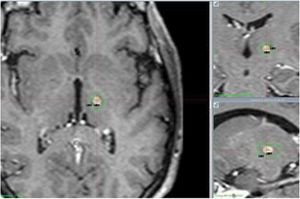

En cuanto a los hallazgos en la RM cerebral de control, a los 12 meses, las lesiones presentan una forma ovalada y el centro de las mismas ha coincidido en todos los controles con la localización del objetivo (target). La media de volumen de tejido hipointenso en secuencias T1 e hiperintenso en secuencias T2 que capta contraste fue de 104 mm3, con una mediana de 91,5 mm3 (fig. 4).